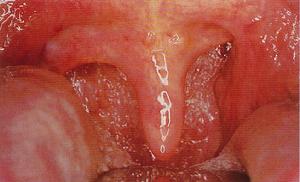

聲帶麻痹與功能性失音的鑑別

(一)聲帶麻痹多為一側性,兩側性光見;而功能性失音為兩側聲帶內收性麻痹

(三)功能性失音在間接喉鏡下檢查,讓患者咳嗽時,聲帶活動正常。